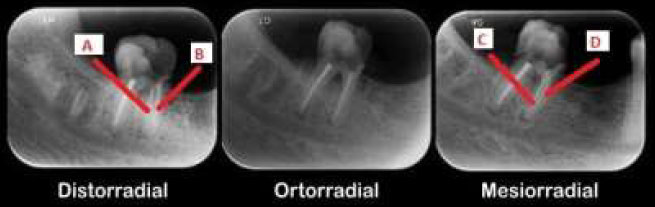

A técnica de Clark tem como objetivo identificar a localização de algumas estruturas da cavidade bucal. Analise a imagem e responda as questões 21 e 22.

I. O canal C está pela lingual e o D pela vestibular.

II. A estrutura que se encontra na frente, acompanha o movimento do feixe de raio X.

I. O canal A está pela lingual, enquanto o B está por vestibular.

II. O canal A está pela vestibular, enquanto o B está por lingual.

III. O canal D está pela vestibular enquanto o canal A está por vestibular.

O canal C está pela vestibular, enquanto o B está por vestibular.